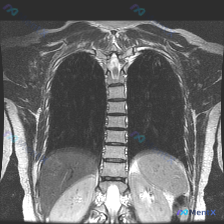

整理到一个很有意思的影像读片材料: 一张胸部MRI-T2序列冠状位影像,原始的影像学分析写的是“胸廓、脊柱、纵隔及肺野解剖结构基本正常,未见明显的病理性高信号改变”,甚至明确提了“椎体信号均匀,骨皮质轮廓清晰,未见明显骨质破坏”。 但拿到这份材料的人,第一眼观察到的线索是——脊柱侧弯(Scolios...

整理了一份影像分析资料,觉得这个矛盾点挺有意思的,拿出来和大家讨论。 资料背景是:一张胸部MRI T2加权像(冠状位),临床核心诉求是排查脊柱侧弯。 先放几个关键的影像所见: - 肺实质、纵隔、胸膜腔、胸壁软组织都未见明显异常信号或占位 - 报告写了“胸椎椎体及附件形态基本完整”、“脊柱旁软组织未见...

整理到一个挺有意思的病例复盘点,想跟大家讨论下临床思维: - 核心场景:患者主诉“脊柱侧弯”,但拿到的一张胸部冠状位T2 MRI报告里写着「胸椎序列排列整齐,左右基本对称,未见明显异常」。 - 影像背景:图像清晰度良好,胸廓、肺野、上腹部显露部分确实没看到积液、肿块或骨髓水肿信号。 问题来了:这种主...

整理到一份胸椎MRI冠状位T2加权的影像资料,先把核心阳性发现和阴性排查点列出来,大家看看思路会怎么走。 核心阳性表现: - 胸椎整体存在轻度侧向弯曲,左右不对称 关键阴性排查(目前MRI层面): - 脊髓信号正常,连续性好,无受压、增粗或中央管扩张 - 各椎体形态规则,骨髓信号均匀,未见压缩骨折、...